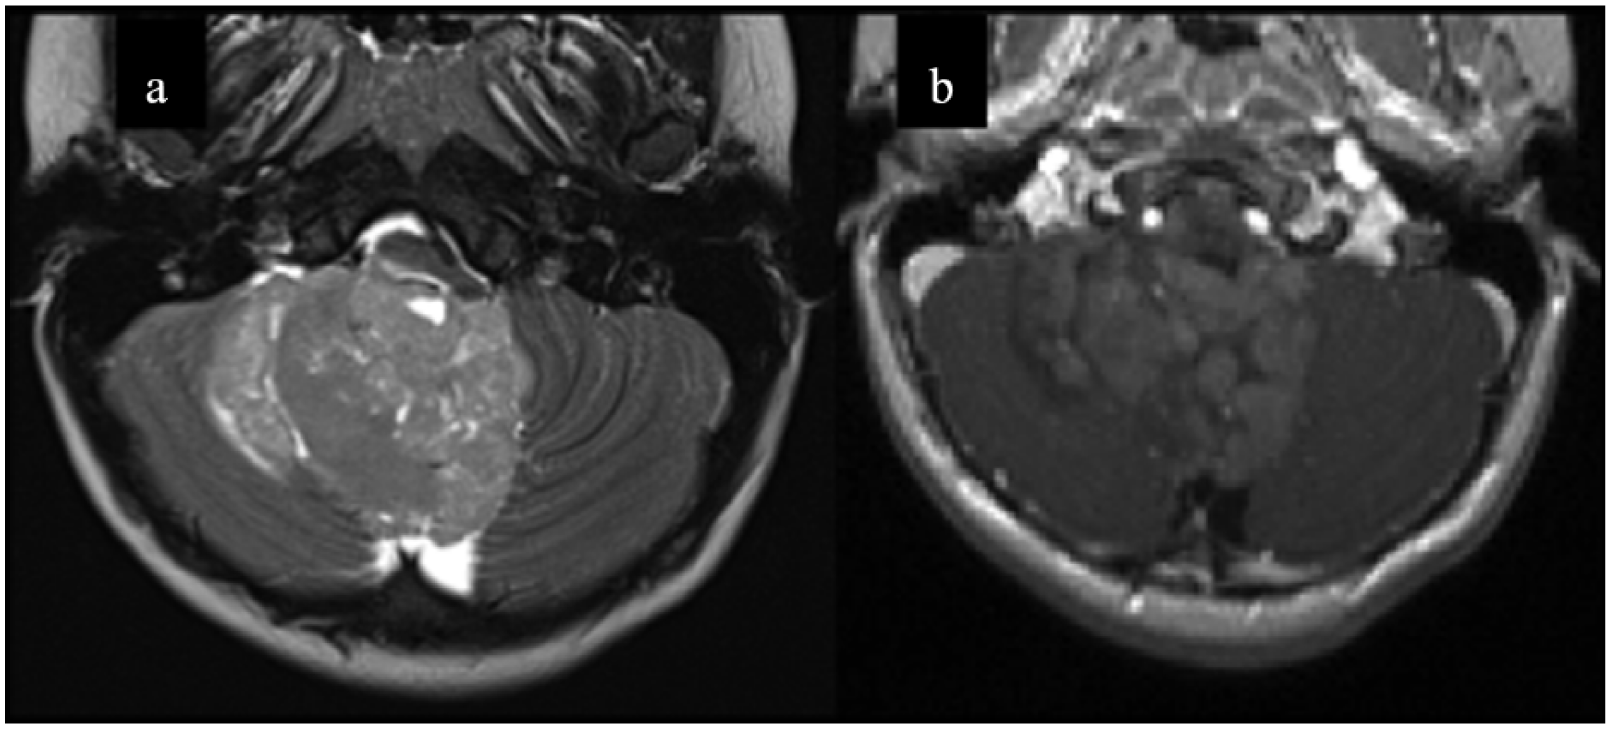

Subgroup SHH represents 28–30% of all medulloblastomas, with a bimodal age distribution: it is more frequent in infants and adults, with a slight male predominance among infants. 28 These patients have an intermediate prognosis, with 5-year survival ranging between 60% and 80%, but the associated mutations in MYCN or TP53 oncogenes worsen the prognosis. 29 D/N and MBEN are characteristically associated with the SHH subtype (Figure 1); however, it is possible to observe classic or LC/A histology. 23 Typical genetic alterations lead to the over-activation of SHH signaling: the most common are the somatic or germline inactivating alterations or the loss of PTCH1 and SUFU, or the somatic missense mutations activating SMO.30,31 A few SHH patients present high-risk disease due to co-amplification of MYCN and GLI2, accompanied by inactivation of TP53. 27 Patients with Gorlin syndrome, carriers of a germline mutation on PTCH1, have a predisposition to develop basal-cell carcinoma and medulloblastoma, especially MBEN. 32 An uncommon presentation of SHH subgroup medulloblastomas has also been reported in patients with rare diseases such as Fanconi anemia. 33

Example of SHH desmoplastic medulloblastoma. Two-year-old boy. Axial T2w(a) magnetic resonance images show an intraventricular mass in the fourth ventricle extending into the right Lushka foramen. Axial T1w postcontrast (b) images show associated heterogeneous contrast enhancement.